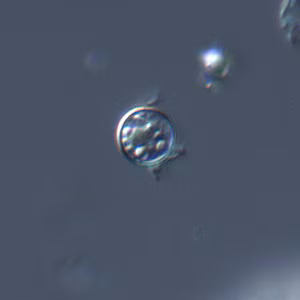

Cyclospora cayetanensis oocysts in wet mounts.

- Wet mounts (by conventional light microscopy, which can be enhanced by UV fluorescence microscopy or differential interference contrast [DIC, Nomarsky])